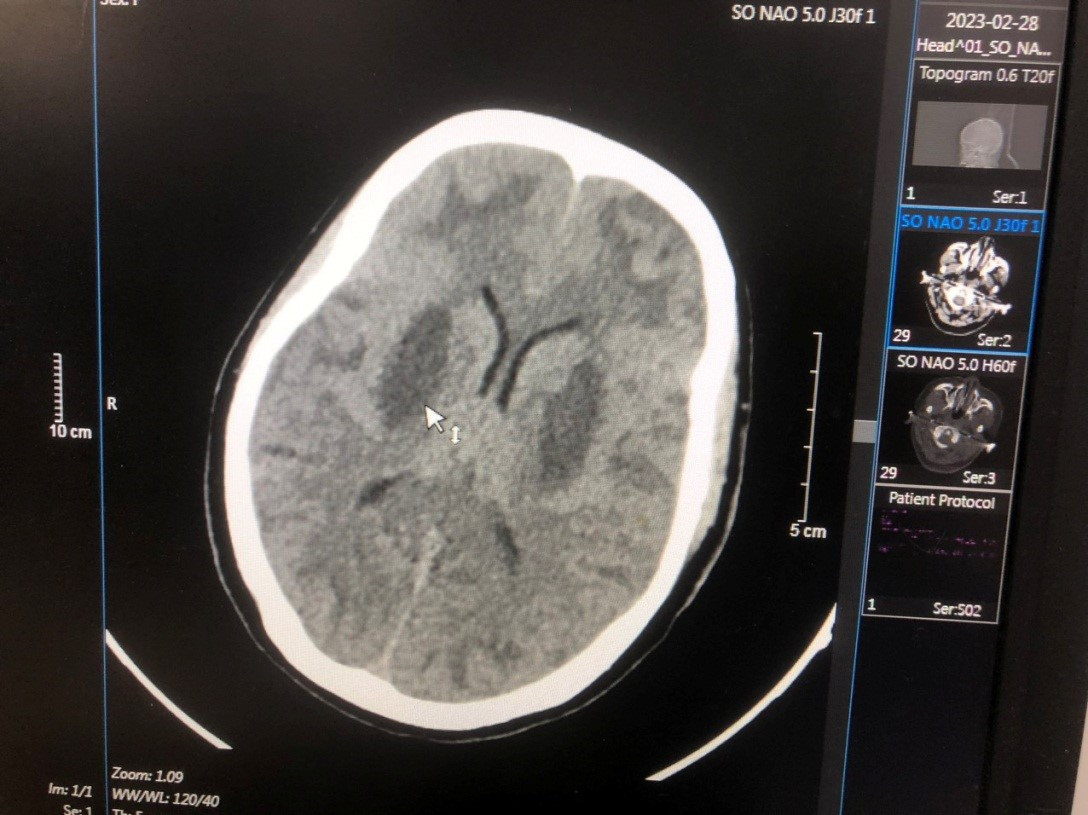

Ngày 28/2, chị được chuyển đến Trung tâm Chống độc trong tình trạng hôn mê, tụt huyết áp, nhiễm toan chuyển hóa nặng, nồng độ methanol trong máu là 123,16 mg/dL, não tổn thương nặng.

Dù đã được điều trị các bác sĩ khẩn trương cấp cứu, hồi sức, giải độc, lọc máu, tuy nhiên, não của bệnh nhân tổn thương nặng không hồi phục. Gia đình xin đưa bệnh nhân về nhà. Sau đó, chị H. đã tử vong.